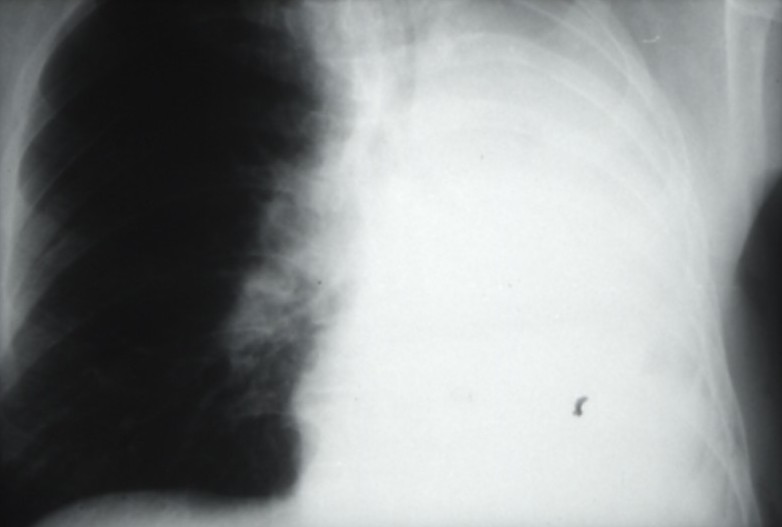

Cancers bronchiques